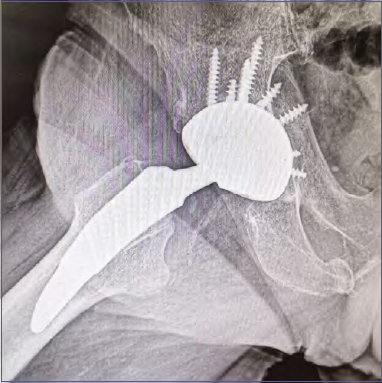

In some cases, prosthetics may be indicated in patients over the age of 75 through the use of multi-hole cups (with bone graft with morselized femoral head positioned on the acetabular fundus); which allow through the screws to perform an internal synthesis of the acetabular fragments (Fig. 8).

Figure 8.Multi-hole cup stabilized with screws.